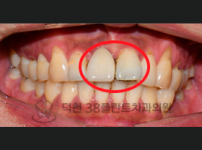

치료전후